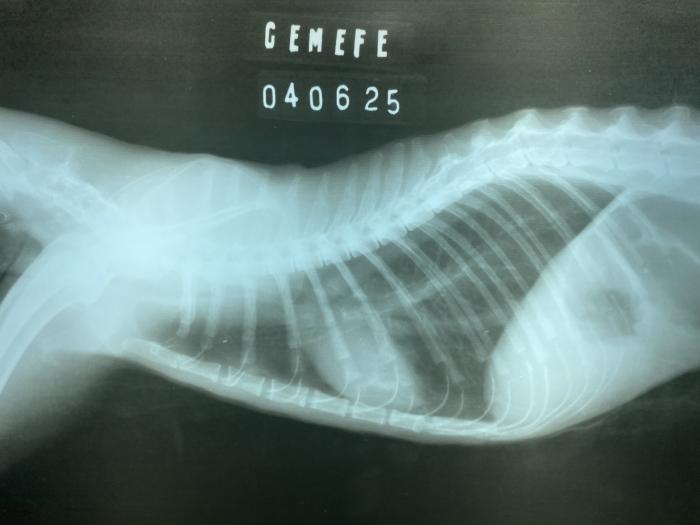

Hay una demora del tercer procedimiento, indicado inicialmente cada 2-4 días, la cual desencadena una complicación no esperada. Originando un aparente cierre completo de la estenosis cervical craneal, el paciente no tolera líquidos ni comidas. La tutora acude a consulta, informando que aparentemente estaría broncoaspirando. Realizamos estudios de imágenes radiográficas, donde se descarta esta posible complicación, pero determinamos el cierre de la estenosis esofágica cervical craneal, con la imposibilidad de colocación de sonda nasoesofágica (sonda de 3.5 F). Luego de varios intentos infructuosos, se comunica este impedimento, con el cual determinamos la estenosis completa, o de mayor gravedad impidiendo el paso de todo tipo de sonda (Figura 6A-C).

Figura 6. (A) Proyección laterolateral de tórax donde descartamos una posible broncoaspiración. (B) Imagen radiográfica obtenida durante el intento de colocación de una nueva sonda de alimentación esofágica. (C) Se puede evidenciar como la punta de la sonda ingresa por el esfínter esofágico anterior. Dilatación del segmento inicial del esófago cervical y caudal a la misma, disminución de la luz esofágica compatible con una estenosis severa.